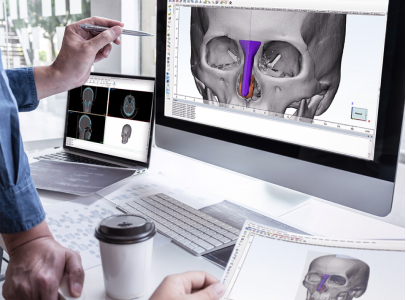

Beyond aesthetics, Dr Goh remains active in reconstructive microsurgery, with expertise in breast reconstruction, head and neck reconstruction, and lower limb salvage—restoring both form and function where it’s needed most.